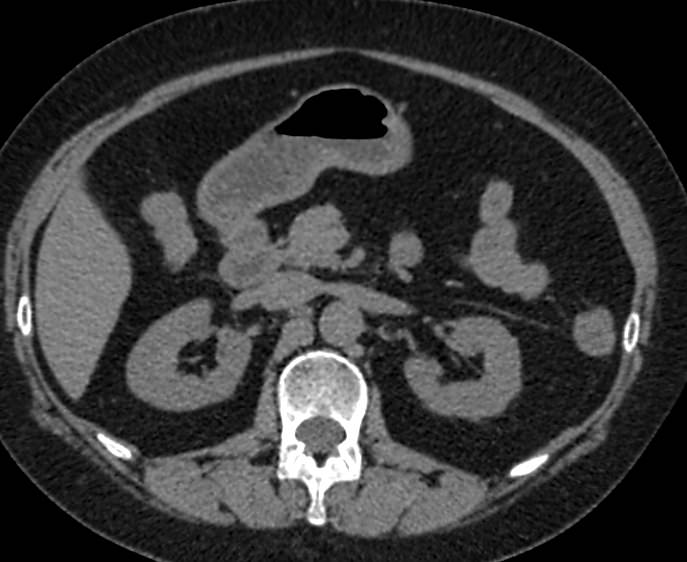

Мультиспиральная компьютерная томография почек и мочевыводящих путей является высокоинформативным методом исследования, основанном на использовании воздействия рентгеновских лучей на органы и ткани человека. Методика предусматривает послойное сканирование области почек, мочевыводящих путей и получение снимков исследуемой области в мельчайших подробностях.

Для улучшения визуализации патологических очагов в некоторых случаях дополнительно применяется контрастное усиление. Для этого пациенту внутривенно вводится йодсодержащее контрастное вещество, которое накапливается в патологически измененных участках и вызывает их яркое контрастирование на фоне здоровых тканей.

МСКТ почек и мочевыводящих путей с контрастированием позволяет выявить опухолевые образования на ранних стадиях, отличить доброкачественную опухоль от злокачественной, определить размеры опухоли, точную локализацию и степень распространения в окружающие ткани. Компьютерная томография почек с внутривенным болюсным контрастированием необходима для определения тактики лечения и объема оперативного вмешательства.